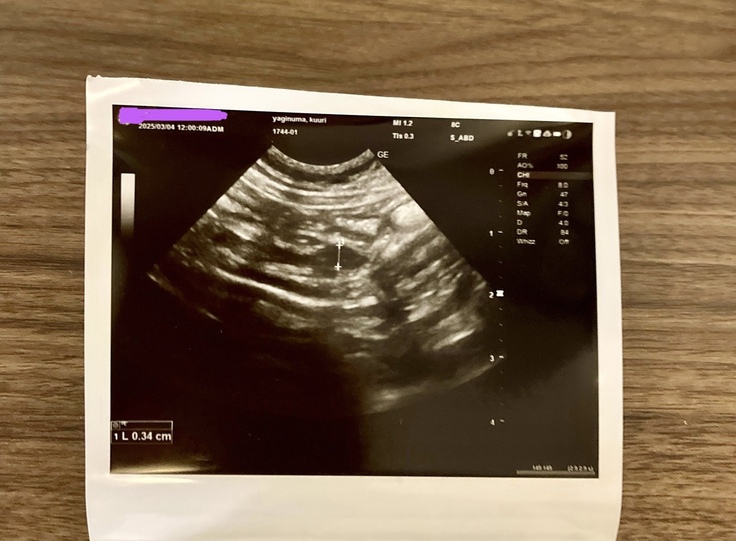

昨日病院に行って来ました。

数値がだいぶ正常値に近づいてきてました。

腸の近くのリンパの腫れだけが、全然小さくなってなくて心配です。

獣医師には、様子を見ましょうと言われました。

昨日はとても寒くて、病院で採血とエコーで

疲れてしまったらしく、帰ったらこんな感じでした。